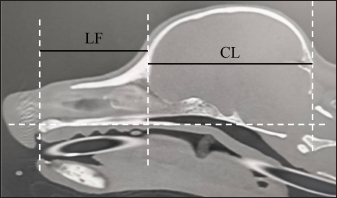

where skull width (SW) is the length between the most lateral points of the zygomatic arch (dorsal section, Fig. 2A) and FL is the length between the nasion and the prosthion (sagittal section, Fig. 2B).

Fig. 2. A and B. CT measurements for FIct. A: SW: the length between the most lateral points of the zygomatic arch (dorsal section). B: FL: the length between the nasion and the prosthion (sagittal section). Window width: 5,000, window level: 1,000.